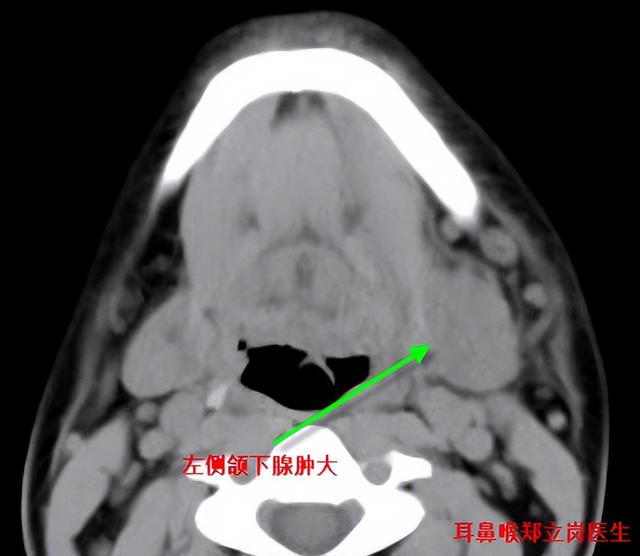

最近来自广东茂名的颜先生由于颌下肿胀找到耳鼻喉郑立岗医生,郑主任看后做了检查诊断为颌下腺炎,由于比较严重,影响进食,收住入院。入院检查后发现患者左侧颌下腺导管中有巨大的结石,炎症就是由于这个结石导致的。

给患者予以消炎、消肿、支持等治疗后,患者的肿胀明显的减轻,在治疗的第二天患者左侧的结石就从口里面排了出来。这么大的结石通过非手术治疗予以排除其实是非常罕见的。